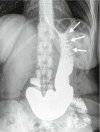

Background and study aims: Bariatric endoscopy has emerged as an aid in the nonsurgical treatment of obesity. The objective of this study is to critically provide the results and follow-up of endoscopic sleeve gastroplasty 1 year after the procedure.

Patients and methods: Prospective single-center follow-up study of 25 patients (5 men, 20 women) who underwent flexible endoscopic suturing for endoluminal gastric volume reduction. A multidisciplinary team provided post-procedure care. Patient outcomes were recorded at 1 year after the procedure. Linear regression analysis was done to evaluate the variables associated with best results at 1 year of follow-up.

Results: Mean body mass index (BMI) was 38.5 ± 4.6 kg/m(2) (range 30 - 47) and mean age 44.5 ± 8.2 years (range 29 - 60). At 1 year, 22 patients continued with the follow-up (2 dropped out at 6 months and 1 at 3 months). There were no major intra-procedural, early, or delayed adverse events. Mean BMI loss was 7.3 ± 4.2 kg/m(2), and mean percentage of total body weight loss was 18.7 ± 10.7 at 1 year. In the linear regression analysis, adjusted by initial BMI, variables associated with %TBWL involved the frequency of nutritional (β = 0.563, P = 0.014) and psychological contacts (β = 0.727, P = 0.025). The number of nutritional and psychological contacts were predictive of good weight loss results.

Conclusions: Endoscopic sleeve gastroplasty is a feasible, reproducible, and effective procedure to treat obesity. Nutritional and psychological interaction are predictive of success.